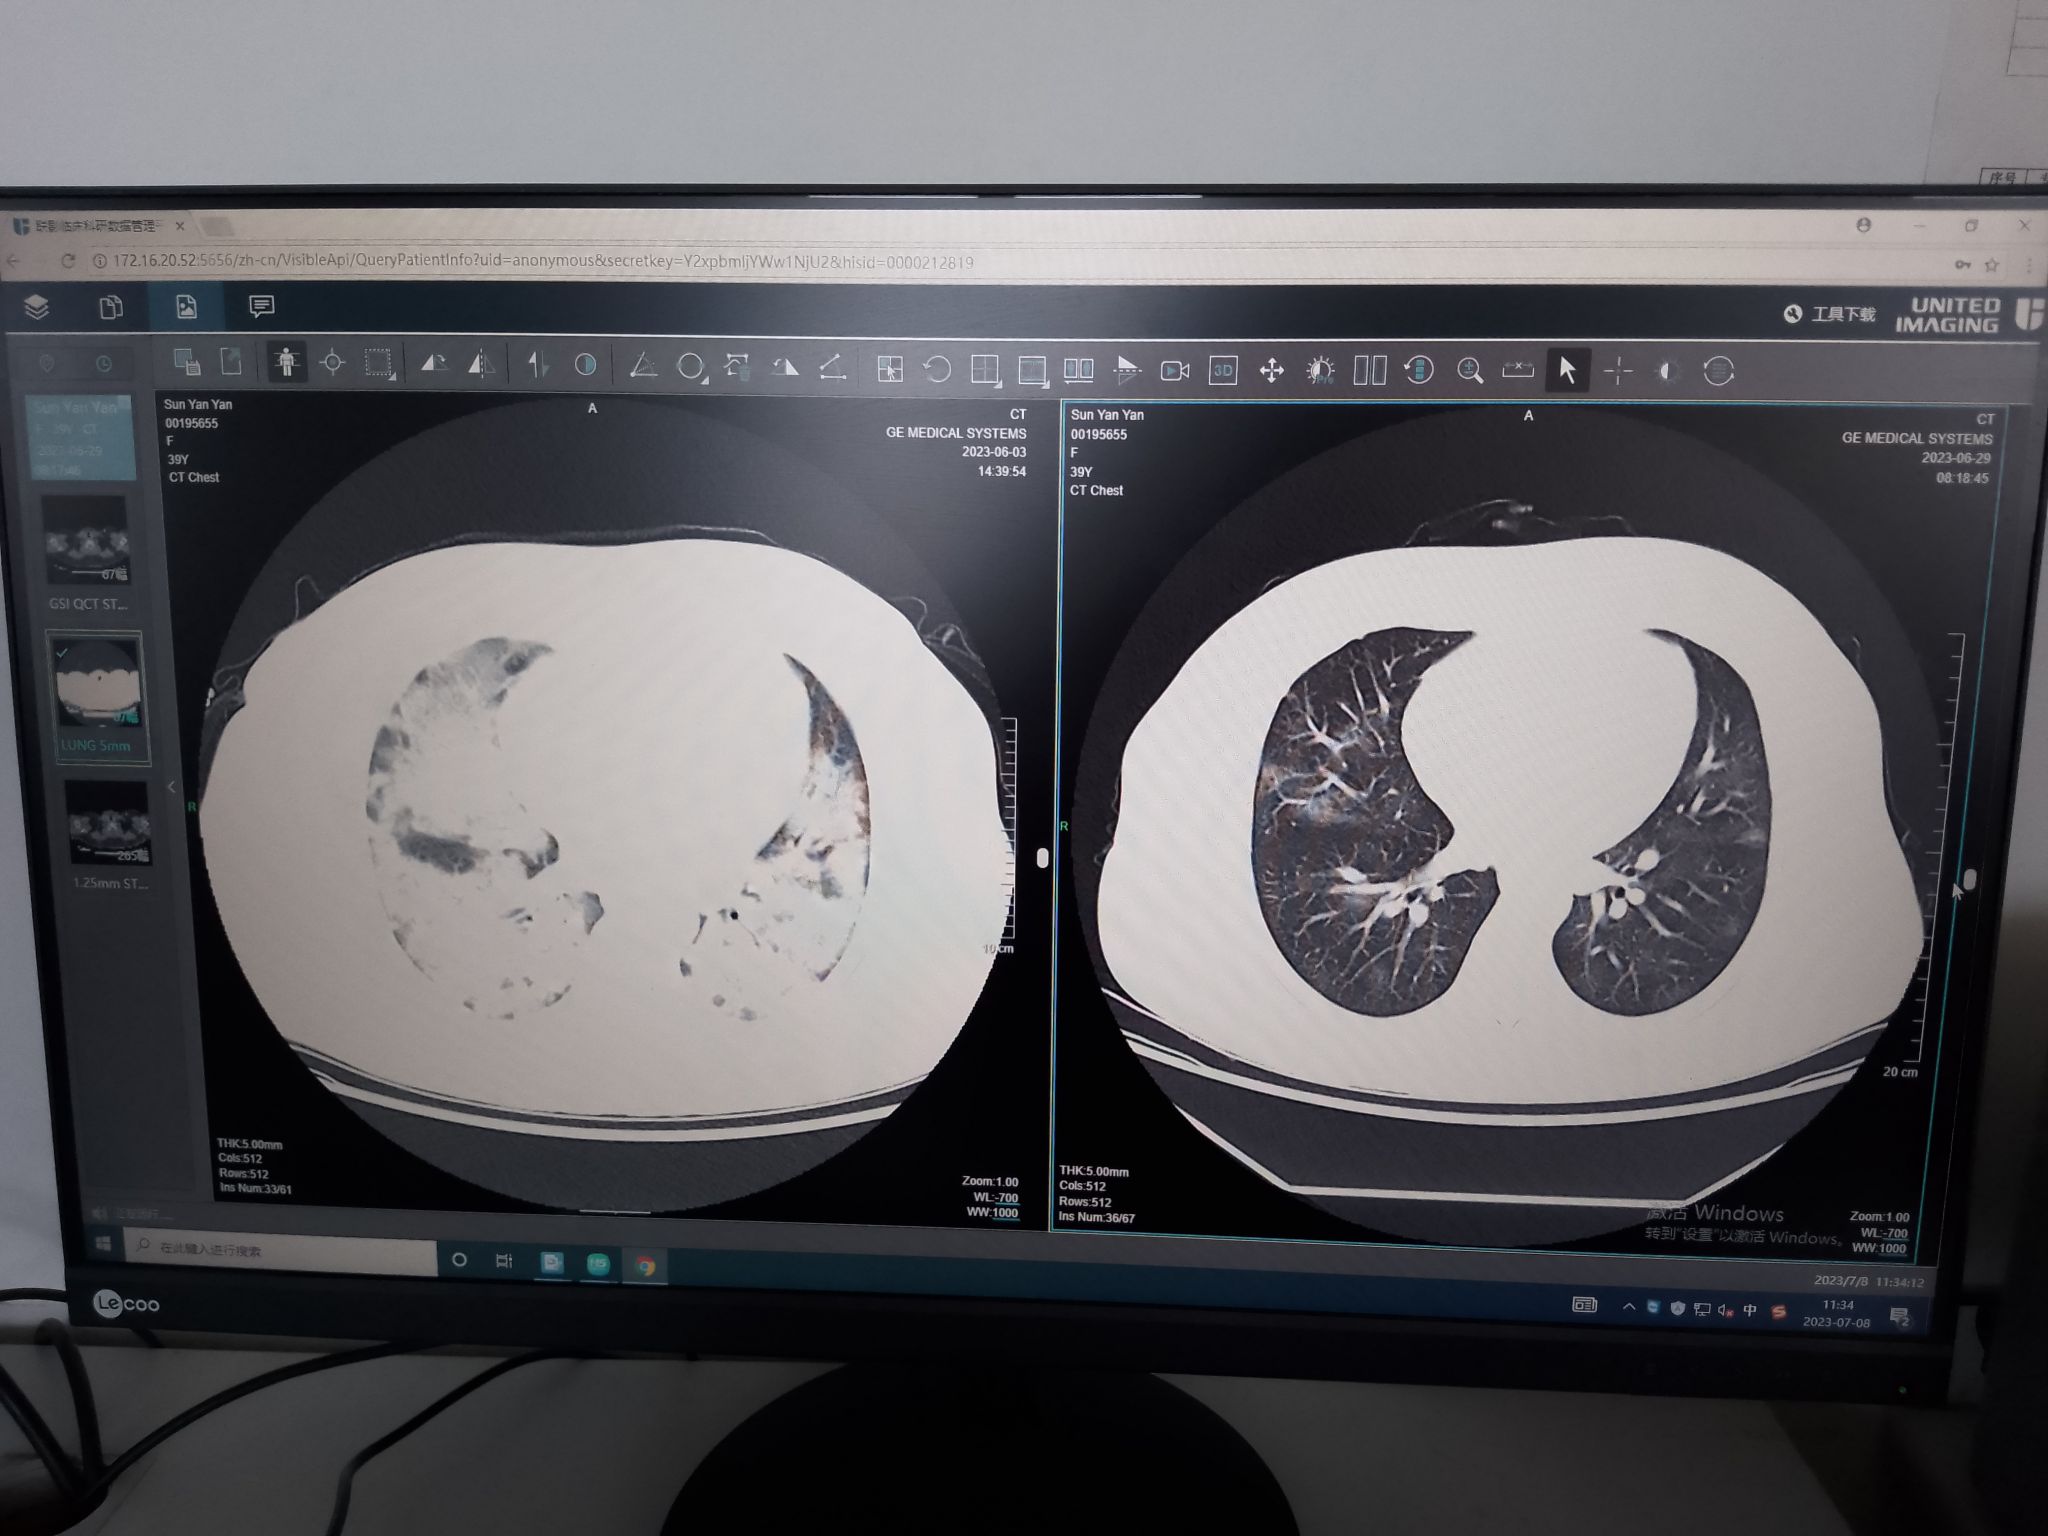

2023年6月2日14时, 已间断发热10天且伴有胸闷憋气的孕妇小孙被送到山一大二附院急诊科,当时她已怀孕27周。入院时该孕妇病情非常危重,高流量吸氧的情况下,外周血氧饱和度也仅仅维持在75%左右(正常人大于95%,低于90%就会出现濒死感)。面对如此危重病人,急诊科第一时间联系产科、呼吸科及重症医学科等多学科会诊,将病人收入重症医学科病房。重症医学科杨慧医师接诊病人后,立即为病人安排完善CT检查,检查结果令医务人员倒吸一口凉气,患者CT影像学显示双肺弥漫性渗出,显示“大白肺”,且患者血氧饱和度持续下降,应用无创呼吸机和高流量氧疗难以维持,一大一小两条生命垂危 ,韩承河主任医师、周亚东副主任医师火速组织抢救。

入院时肺部与下机后肺部CT对比

患者肺功能逐渐好转,6月15日患者成功拔出气管插管,自主呼吸平稳,复查胸部CT双肺渗出已明显吸收,病情平稳。医务人员看到复查结果欣喜万分,这位年轻的妈妈重获新生,而且基本上未遗留任何明显的后遗症,创造了医学上的奇迹!